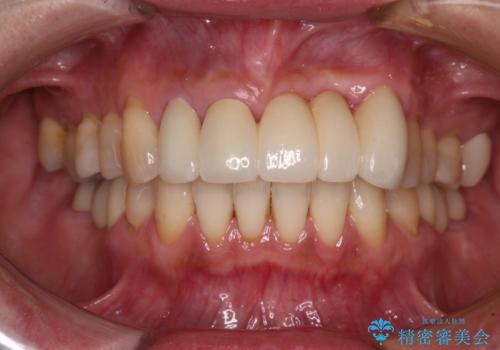

[ セラミック・インプラント全顎治療 ] 長年悩まされている歯の治療にケリをつけたい

![[ セラミック・インプラント全顎治療 ] 長年悩まされている歯の治療にケリをつけたいの症例 治療後](https://seimitsushinbi.jp/wp/wp-content/uploads/2022/01/f4f9ee9ff7018c558de74748d97a4667-500x350.jpg?v=1642042445)